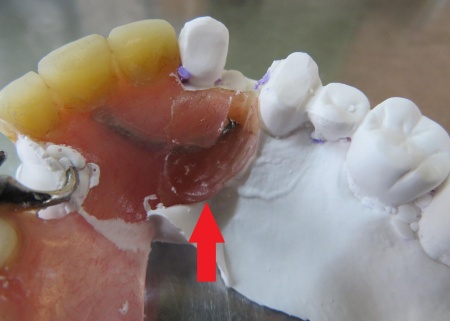

続いて、左上の前から4番目の歯に合わせて金属ワイヤーを成形し、新しいクラスプを作製します。

歯の形にぴったり沿うよう細かく調整し、入れ歯をしっかり支えられる強さに仕上げました。

最後に入れ歯を装着し、痛みや違和感がないか、見た目や噛み合わせに問題がないかを確認し、治療を終了しています。